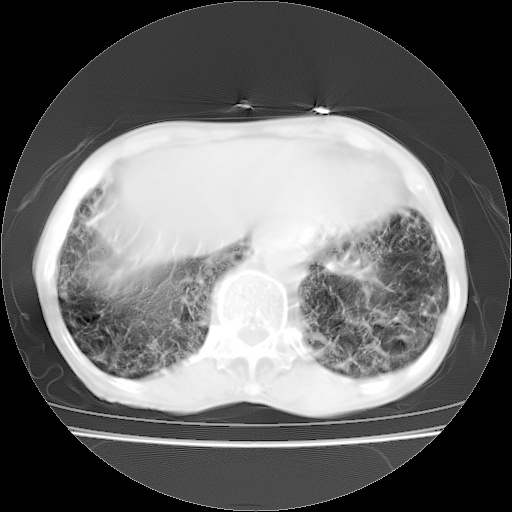

病人发热、气促就诊。原二周前已行ct扫描,当时诊断为双肺下叶、右肺中叶支气管扩张并感染,双肺上叶片状渗出性病变。今天复查胸部ct,双肺下叶支气管扩张并感染病灶较前明显吸收,但双肺上叶渗出性病变较范围较前明显增大。

现传今天ct图像给大家讨论。

双肺多发大片状、斑片状高密度渗出影,部分实变,考虑病毒性肺炎。